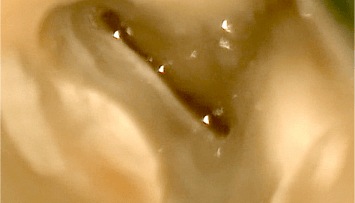

Die Endodontie hat in den vergangenen Jahren einen immensen Fortschritt erlebt. So können heute mit Zuhilfenahme moderner Geräte und Techniken auch Zähne erfolgreich erhalten werden, die noch vor geraumer Zeit als nicht erhaltungsfähig galten.